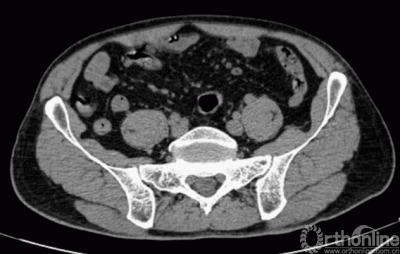

患者术前CT三维重建图像

由AI HIP系统对患者的髋关节CT数据进行人工智能分割与关键点识别,术者可根据智能分割与测量结果综合判断患者情况。如图可见,该患者关节内可见明显畸形。